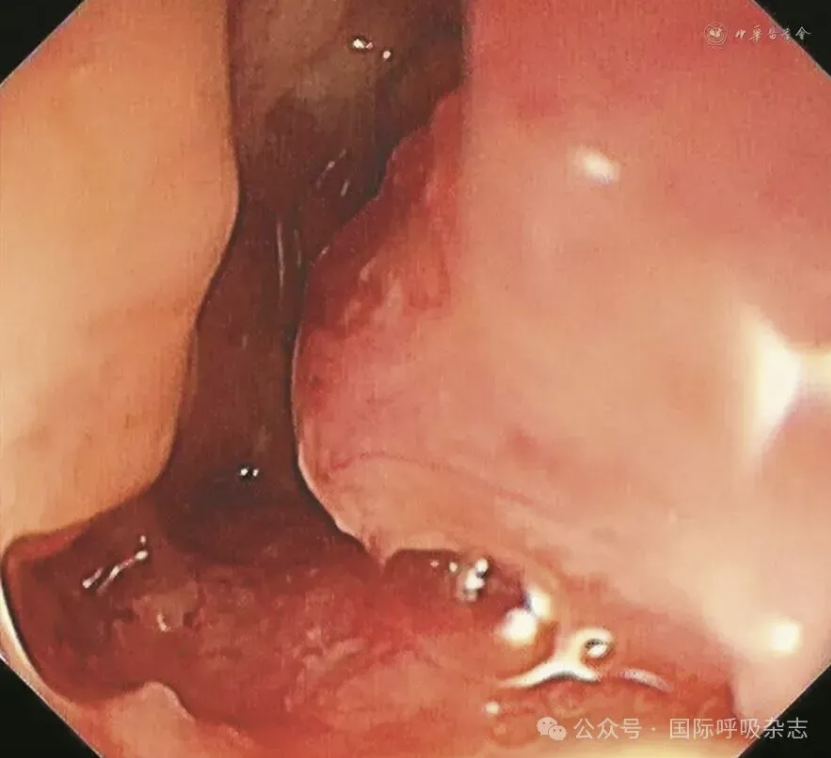

患者男,61岁,因“食管癌术后3年,咳嗽、气喘半年”于2025年3月14日入院。患者于2022年确诊食管鳞癌,曾接受新辅助免疫联合化疗、食管癌根治术、术后辅助免疫治疗、局部放疗及多线化疗等规范治疗。2024年12月经胃镜检查确诊为“气管食管瘘”,遂行空肠营养管置入术(图1)。后因咳嗽、气喘症状持续,辗转多家医院治疗效果不佳就诊于西安市胸科医院。入院查体:端坐呼吸,声音嘶哑,双肺可闻及湿性啰音及喘鸣音。实验室检查示炎症指标升高:白细胞计数8.82×109/L,中性粒细胞比例88.8%,C反应蛋白165.88 mg/L。血气分析pH值7.435,PaCO2为45.2 mmHg(1 mmHg=0.133 kPa),PaO2为55 mmHg,氧合指数200 mmHg,提示Ⅰ型呼吸衰竭。胸部CT提示气管食管瘘,伴双下肺感染及实变(图2)。支气管镜下见气管中下段膜部菜花样新生物,新生物下方可见瘘口(图3)。

图3:61岁男性气管食管瘘患者支气管镜检查(2025年3月15日)示气管中下段膜部可见菜花样新生物,于新生物下方可见气泡冒出,考虑瘘口形成

经院内多学科诊疗(胸外科、肿瘤科、影像科、消化科等),确定行气道支架置入术治疗气管食管瘘,其中气道支架的大小及种类选择决定手术成败。通过气道三维重建(气管上中段管腔狭窄,长度约45 mm,狭窄上端距声门下约58 mm,狭窄下端距隆突约28 mm,最窄内径约12.8 mm×3 mm;气管上段距声门下腔约82 mm处可见管壁破损,与食管相通,瘘口宽约2~3 mm)(图4)及多次支气管镜下的测量数据,最终确定气道支架型号为:金属覆膜20 mm×60 mm。2025年3月17日行气管新生物电凝圈套切除及消融治疗(图5)。2025年3月20日在全身麻醉硬质支气管镜下成功置入气道金属覆膜支架(图6),术后患者呛咳症状即刻缓解。